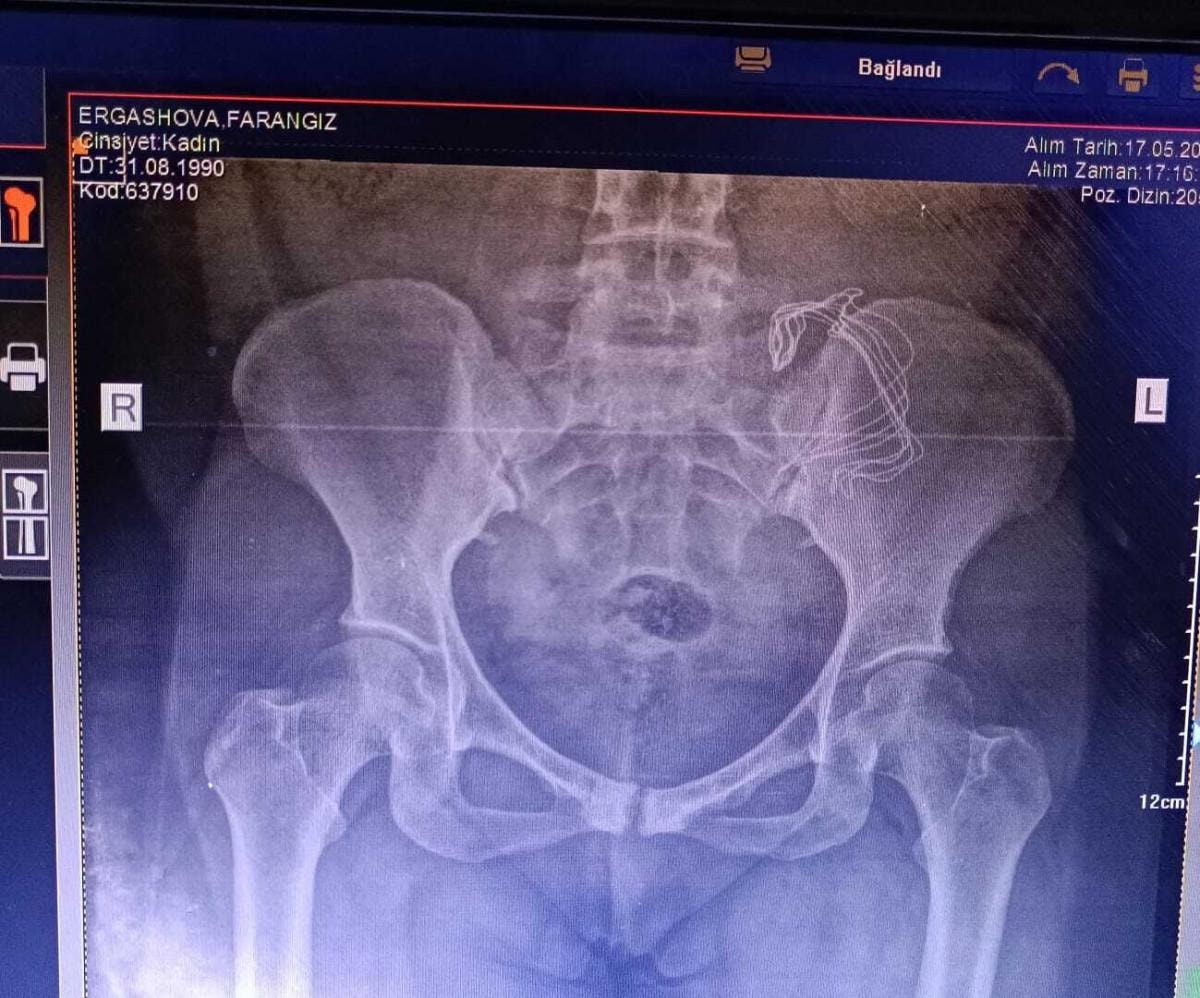

Şikayetlerini doktora anlatan Ergashova'dan tomografi çektirilmesi istendi. Tomografiye bakan doktor, Ergashova'nın karnın sol tarafında yabancı bir cisim olduğunu fark etti.

Hastanede yapılan kontrollerde ve çekilen tomografiden sonra Frangiz Ergashova ameliyata alındı. Ameliyattan sonra Ergashova'nın karnında, doğum sonrası unutulan 15 santimetre büyüklüğünde gazlı bez olduğu ortaya çıktı.

Konuyla ilgili konuşan anne Farangiz Ergashova, "Ağrılarım başladı, akıntı oluyordu sürekli, doğumdan sonra normal olabileceğini düşündüm. 2. doğumumdu. 2-3 ay geçti hala devam ediyor ve iyi değilim, belim ağrıyor. Sonra eşim beni hastaneye götürdü, hastanede de aynı şekilde anlattım. Yabancı cismi hissettiğimi söyledim, bir ağırlık var dedim, kabız olabilirsin dediler. Bana antibiyotik yazdılar. İlaçlar antibiyotik olduğu için emziremedim çocuğu ve sürekli mamayla besledik. Ağrılarım olduğu için çocuklarıma bakamıyordum. Başka bir hastaneye gittik sertliği söyledim, tomografi çekildi, ameliyat olmanız gerekiyor dediler. Ameliyatta sargı bezi gibi bir şey çıktı ve iltihaplanmış. 15 cm. sargı bezi var dediler. Sargı beziyle gezmişim, İçimde iltihaplanmış. İki çocuğum annesiz kalabilirdi. Ölümden döndüm diyebilirim." dedi.